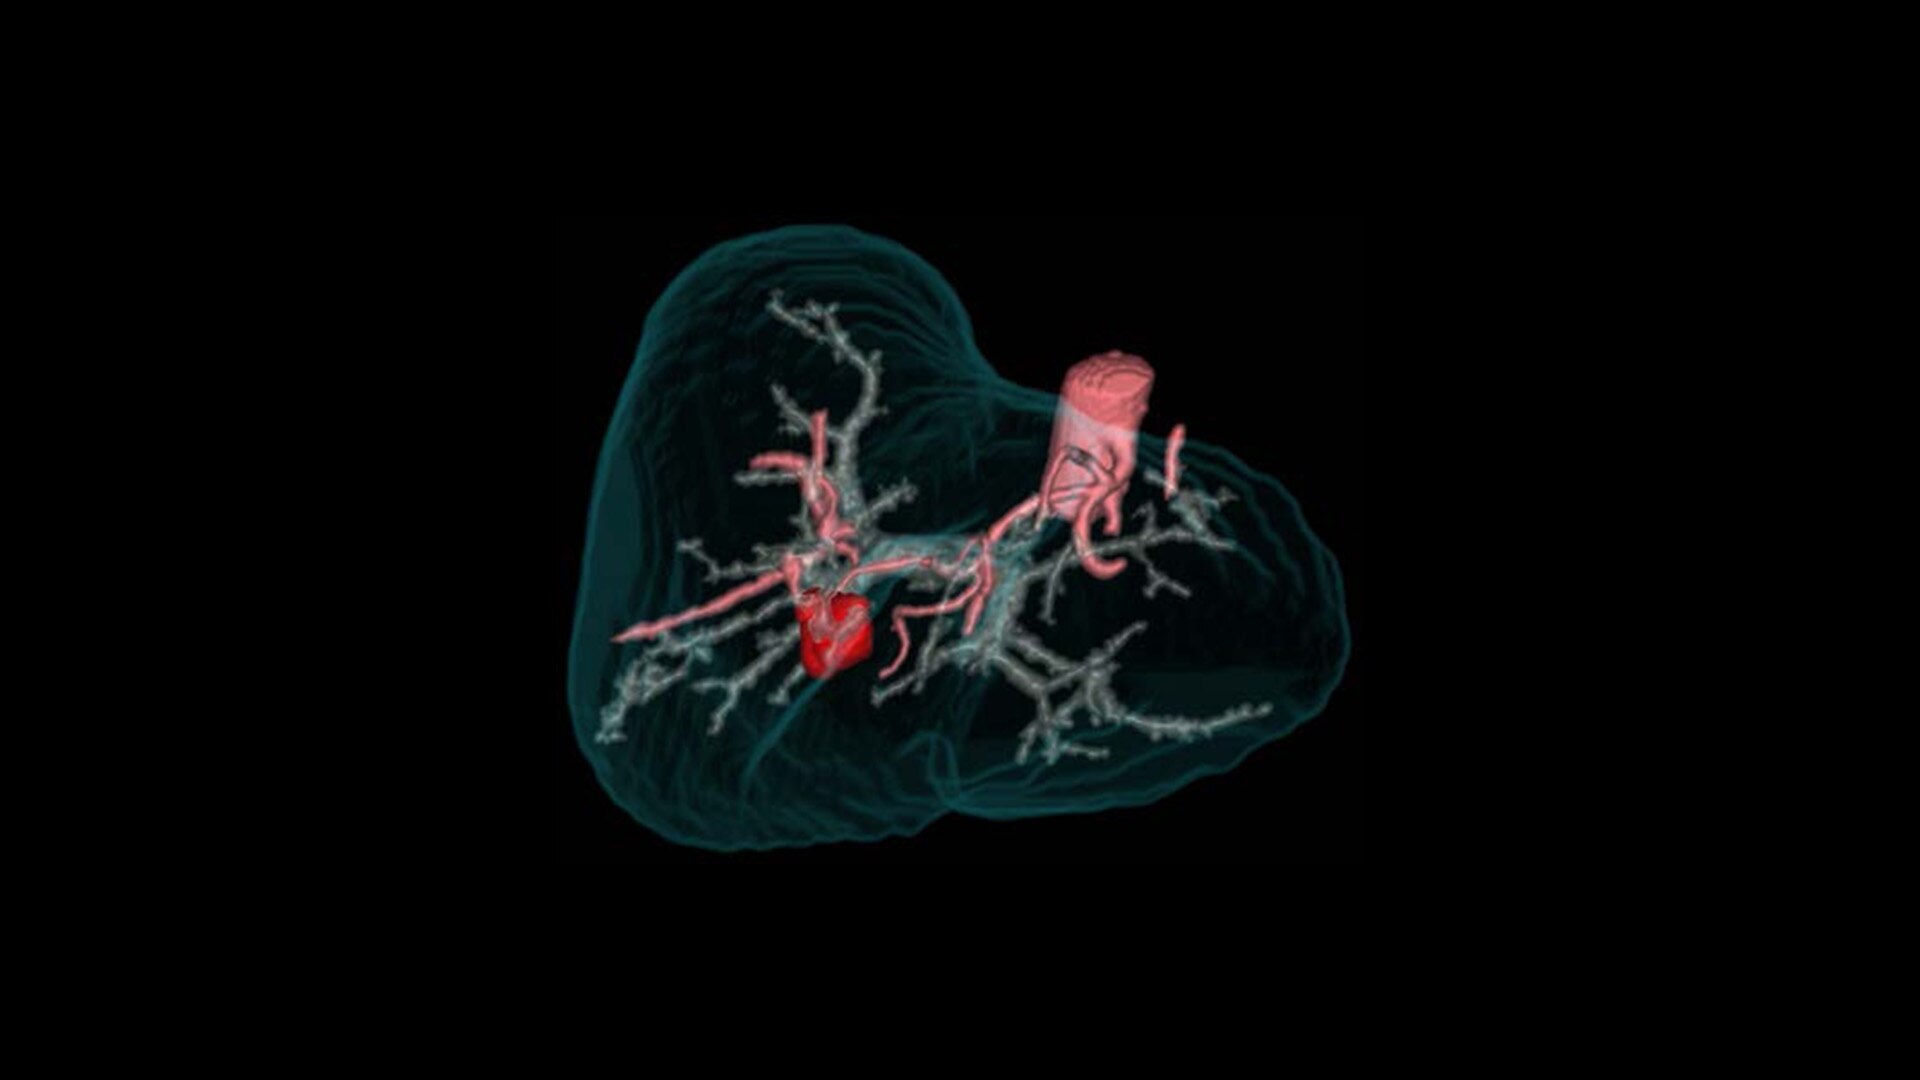

True Enhance DL

Designed to enhance what matters

True Enhance DL is a deep learning-based processing method intended for contrast enhancement of single energy images. True Enhance DL uses a dedicated Deep Neural Network (DNN) trained to estimate monochromatic, 50 keV GSI images from single-energy X-ray. This technology brings four deep learning models that the user can choose depending on different contrast enhancement phases by clinical tasks.